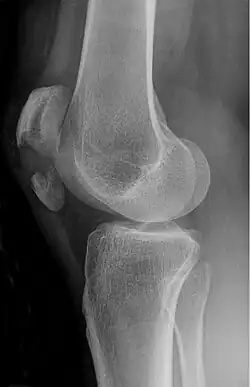

Röntgen

Mit einfachen Röntgenbildern des Kniegelenks in zwei Ebenen (von vorne und von seitlich) kann zuverlässig jeder Kniescheibenbruch diagnostiziert werden. Es zeigen sich die Bruchstücke auseinandergezogen und meist mit einem einfachen Quer- oder Schrägbruch, der der typischen Krafteinwirkung von vorne und dem einwirkenden Muskelzug entspricht. Damit liegt auch die Zerreißung der knorpeligen Gelenkfläche der Kniescheibe zur Oberschenkelrolle („patellares Gleitlager“) vor.

Bei höherer Krafteinwirkung wie z. B. bei Verkehrsunfällen oder bei schlechter Knochenstruktur (Osteoporose) kommt es zu so genannten Mehrfragmentbrüchen oder Sternbrüchen, die eine wesentlich größere Zerstörung von Knochen und Gelenkfläche bedeuten, im Prinzip aber primär die gleiche Auswirkung auf die Kniefunktion haben.

Im Röntgenbild ist die Darstellung der Mehrfragmentfraktur unsicherer, trotzdem ist hier weitere bildgebende Diagnostik mit CT oder Kernspin für einen Chirurgen nicht immer sinnvoll: Während der auf jeden Fall notwendigen Operation kann man offen alle einzelnen Fragmente identifizieren und entsprechend versorgen.